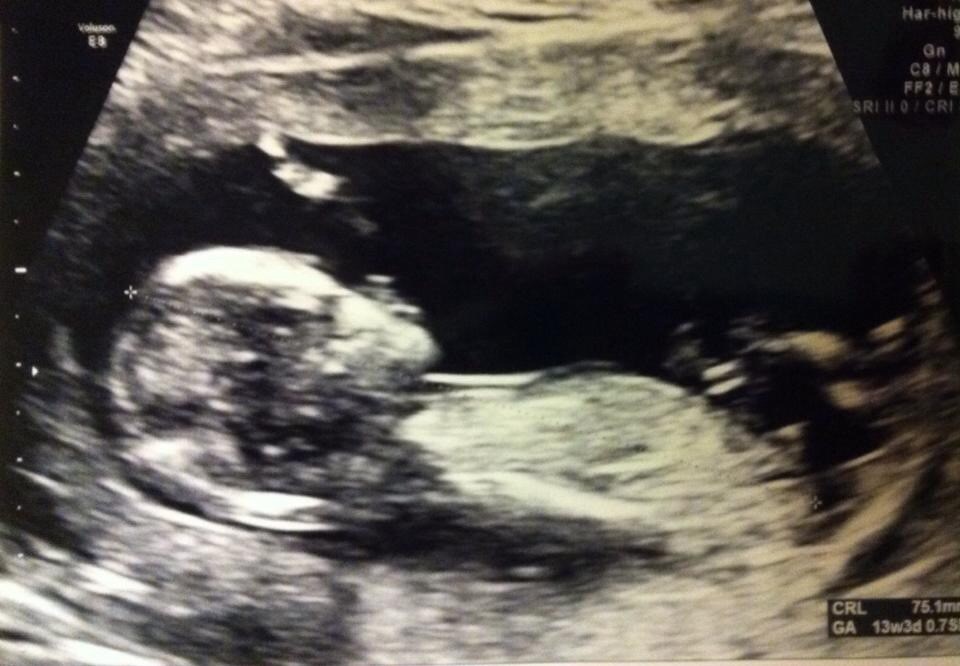

Man kunne se arme, ben, krop og hoved og til tider navlestreng og selvfølgelig et lille hjerte blinke.

Den bevægede sig ikke rundt, men hun sagde at det kunne være at om 5 min så lå den slet ikke stille -men hun var glad for at den lå stille ellers kunne hun ikke måle :-)